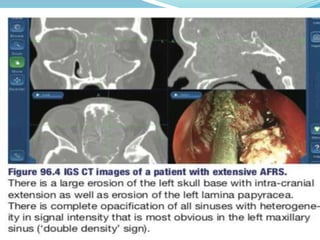

IMAGING โ€“ COMPUTEDTOMOGRAPHY (CT) AND MAGNETIC RESONANT IMAGING (MRI) SCANS

๏‚— CT withoutcontrast is the imaging of choice. ๏‚— The focal or diffuse areas of hyperintensity seen on CT are due to calcium and manganese deposits in the necrotic debri of the fungus and allergic mucin. ๏‚— This results in a โ€˜double densityโ€™ or rail-track sign

๏‚— MRI withintra-venous gadolinium contrast can be considered when the diagnosis of AFRS is uncertain or if there are intra- cranial or intra-orbital complications. ๏‚— The protein content and viscoity of the secretion will determine the signal intensity seen on MRI. ๏‚— In fungal infections, the consistency of the secretion usually results in a low intensity on T1 and a much lower intensity to signal void on T2 . ๏‚— This is due to higher concentration of iron and manganese as well as calcium deposits within the fungal concretions.